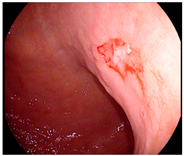

Detailed endoscopic clipping procedures have been described previously [12,13], and ICG injection and hemoclip application were performed at the same time on the day before surgery. As previously reported [14,19,24,25], we endoscopically injected ICG (Dongindang Pharmaceutical Co., Siheung-si, Korea) solution into the gastric submucosal layer at four quadrants around the tumor, on the day before performing NIR fluorescence-guided surgery. Each of the four quadrants was injected with 0.6 mL of 0.625 mg/mL ICG solution for a total of 1.5 mg of ICG. In addition, endoscopic hemoclips were used to grossly delineate the tumor. Two hemoclips were placed proximal to the tumor (Figure 1).

Figure 1.

Preoperative tumor localization: (a) endoscopic identification of the tumor; (b) submucosal ICG injection around the tumor in each quadrant; (c) additional application of hemoclips proximal to the tumor.